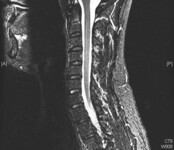

Doença degenerativa da coluna cervical

Compressão da medula espinhal prévia em C3/4 na ressonância nuclear magnética (RNM) sagital de T2, com alterações residuais em T2 e nova compressão em C2/3 e C6/7, com alterações em T2

Dennis A. Turner, MA, MD